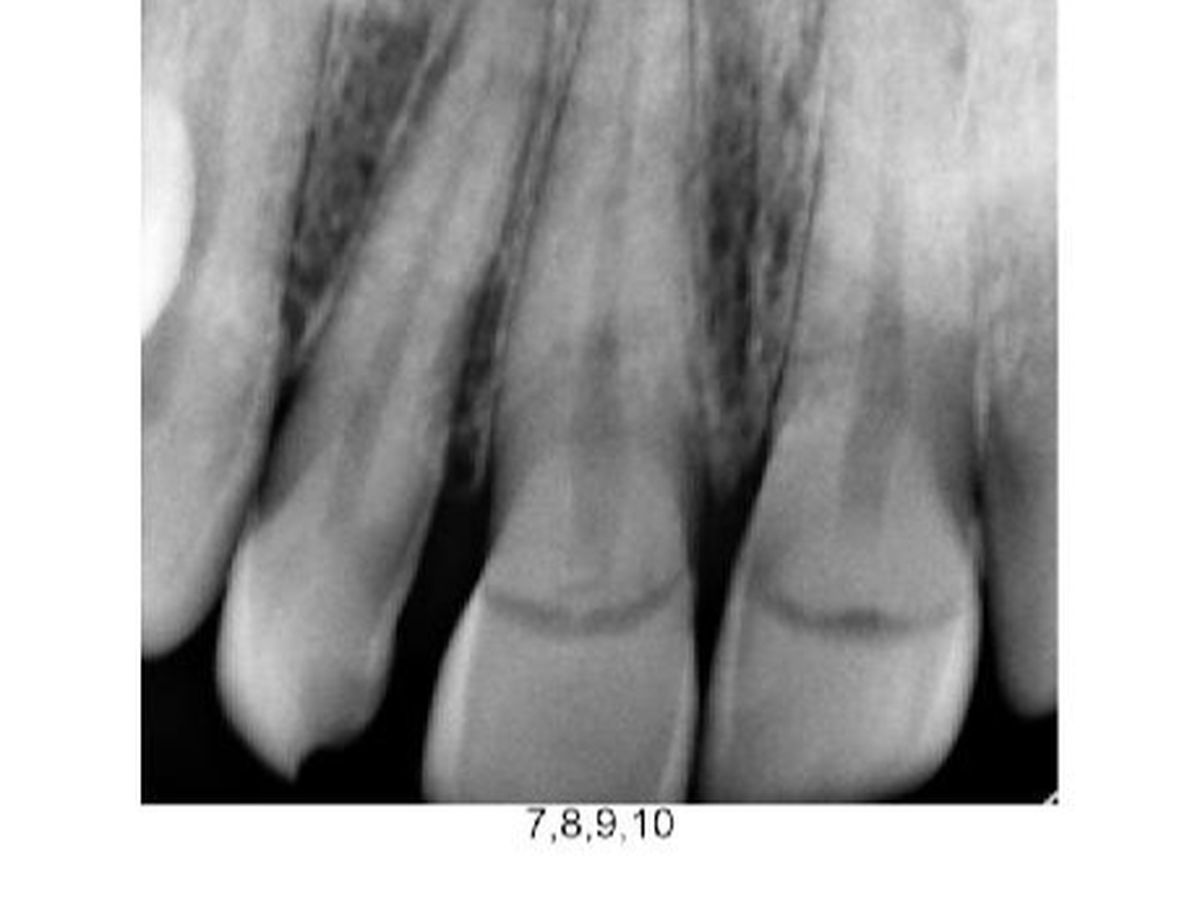

Hi Everyone ! The Elrod family is reaching out to our community to help a friend in need . We’re raising money for KT’s two front teeth +1 . Her and Luna took a good tumble on the sidewalk after visiting some Christmas lights . KT ( or as Luna calls her Titi ) ,being selfless, took the brunt of the fall supporting Luna’s head up leaving her defenseless to catch herself ; resulting in a face plant and knocking out Titi’s two front teeth , shifting and cracking a third one ... That all being said , Luna didn’t have a scratch on her .Although we’re devastated to see her have to go through so much pain ,we also find ourselves so thankful. Emergency bills , 2 teeth implants , reposition and bonding on the third has added up … this is where we come in . If you know KT , you know that she’s the first to open her home and wallet to those in need . Hopefully, we can come together and do the same . Every bit counts and even the smallest amounts are appreciated .